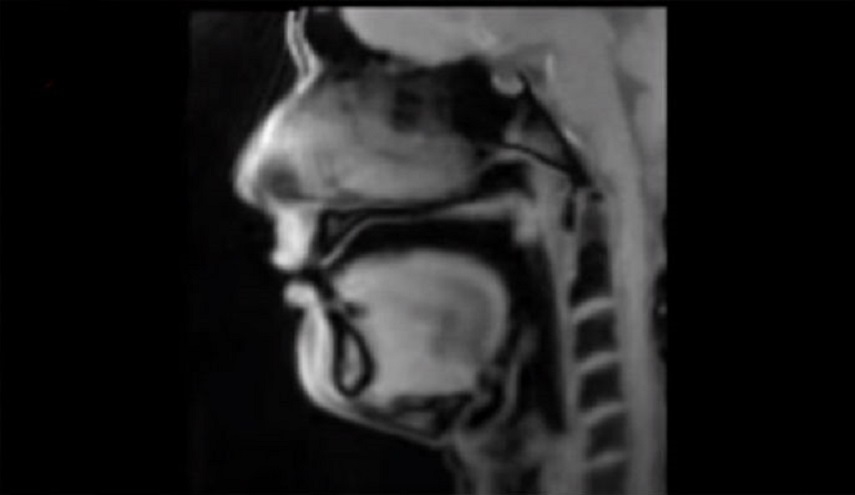

علوم وتكنولوجيا-الكوثر: أصدر باحثون من معهد ماكس بلانك مجموعة من مقاطع الفيديو الرائعة التي تصور العمليات البيولوجية في جسم الإنسان من الداخل، للمرة الأولى على الإطلاق.

وتمكن الباحثون من تصوير هذه المقاطع باستخدام نوع جديد من تقنيات التصوير بالرنين المغناطيسي التي تنتج الصور المتحركة في الوقت الحقيقي.

ويتميز "FLASH2" بأن له تأثيرا مماثلا، لأنه يقدم للعلماء والمهنيين الطبيين والخبراء، أول صورة متحركة للرنين المغناطيسي في الوقت الحقيقي، بمعدل يصل إلى 100 إطار في الثانية.

وبشكل جوهري، تم تحويل التصوير بالرنين المغناطيسي (MRI) من الصور إلى مقاطع الفيديو، وقُدمت أول مقاطع فيديو ثلاثية الأبعاد لـ "نبض القلب والمفاصل المتحركة"، بالإضافة إلى عمليات بيولوجية مثيرة للإعجاب مثل البلع أو طريقة التحدث.